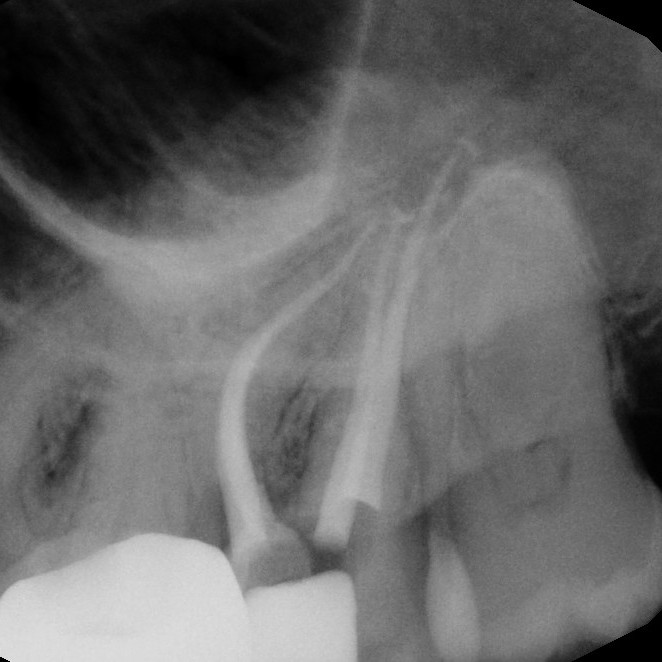

Endodontic surgery is a specialized dental procedure used to treat problems at the tip of a tooth's root or in the surrounding bone when standard root canal therapy isn't enough. The most common type, called an apicoectomy, involves making a small opening in the gum to access the root tip, removing infected tissue, and sealing the end of the root to prevent the infection from returning. This allows us to save the natural tooth and restore oral health, even in cases where other treatments have failed.

While it may sound complex, modern endodontic surgery is precise, minimally invasive, and performed under local anesthesia for your comfort. Most patients are surprised at how quick and straightforward the procedure is, and recovery is typically fast. Choosing endodontic surgery can help you avoid extraction, preserve your natural bite, and prevent the need for more extensive dental work in the future.